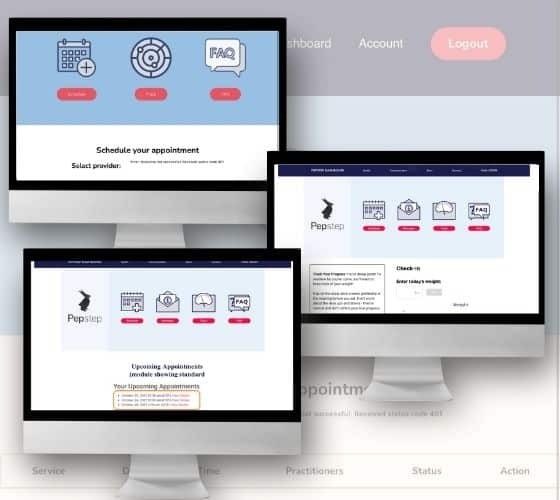

READ MOREWeight Loss Consultation Platform with

Weight Loss Consultation Platform with Appointment Booking and Chat Support Developed a weight loss consultation...